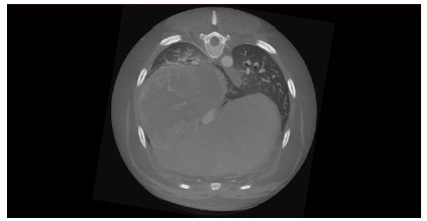

Les scanners classiques fonctionnent avec un mouvement hélicoïdal en mesurant usuellement 1 mm et en extrapolant 1 mm informatiquement. Ce tomodensitomètre atteint le plus haut niveau d’évolution de la technologie CT à écran plat, offrant une imagerie diagnostique de qualité pour les tissus durs et mous. Grâce à sa technologie HDVI, cet appareil d’examen tomodensitométrique exclut l’interpolation en réalisant 100 % de mesure pour créer une reconstruction en 3 dimensions (3D) complète

Il est particulièrement adapté aux Nouveaux Animaux de Compagnie (NAC) en raison de sa rapidité de mesure (une mesure en 22 secondes) et de sa précision au dixième de millimètre près. Un technologie de faisceaux coniques (Cone Beam Technology) permet de réduire l’exposition de l’animal.